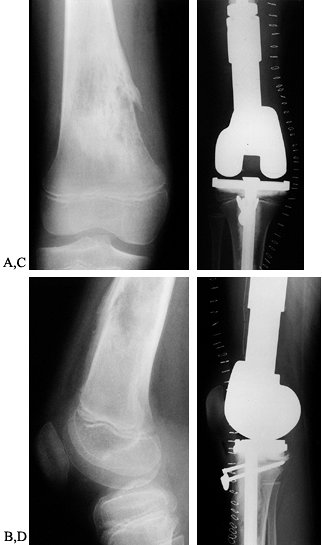

Figure 126.10. A: AP radiograph of the knee and proximal tibia from a 15-year-old boy. An osteosarcoma involves the upper tibia. B: Lateral radiograph of tibial osteosarcoma. C:

AP radiograph after resection of the upper tibia (intra-articular) and allograft arthrodesis. Note the intramedullary rod and screws for fixation. D: Lateral radiograph showing fusion of the knee. |